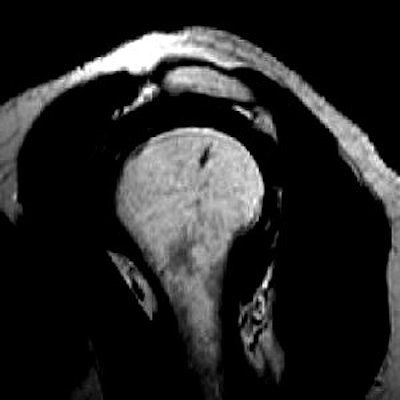

![]() ![]() ![]() |

| A 63-year-old man with impingement syndrome of shoulder. Whereas outlet view radiograph (top) depicts curved acromion (type 2), MR image (middle) in position S-1 reveals blunt acromial hook (type 3), which is also confirmed by 3D model (above) and intraoperatively. Mayerhoefer ME, Breitenseher MJ, Roposch A, Treitl C, Wurnig C, "Comparison of MRI and Conventional Radiography for Assessment of Acromial Shape" (AJR 2005; 184:671-675). |